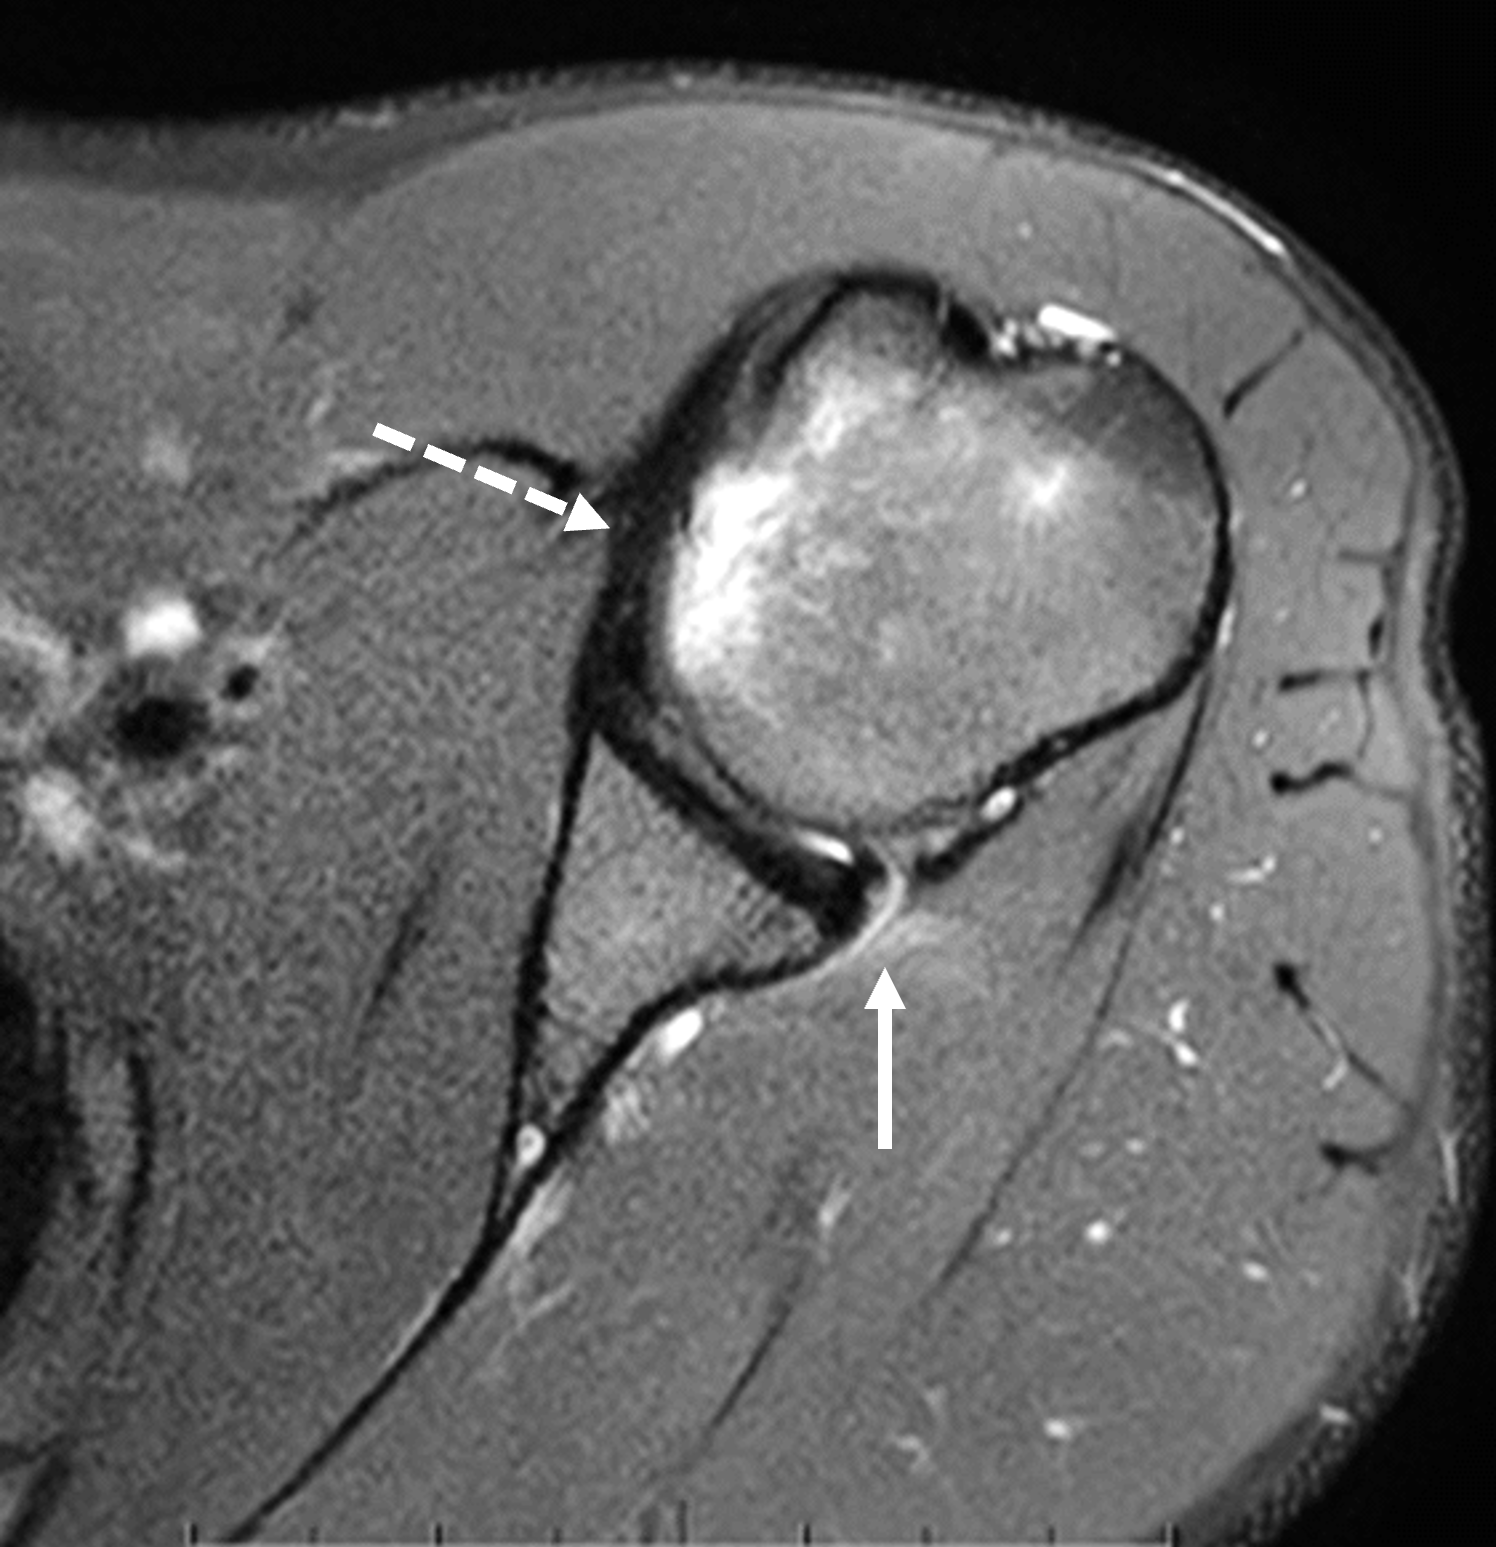

Le immagini assiali (2A e 2B) mostrano i riscontri di una lesione da instabilità gleno-omerale posteriore, tra cui lacerazione capsulo-labrale posteriore-posteroinferiore ed edema pericapsulare (frecce continue) e una lesione da impatto della testa omerale anteromediale (frecce tratteggiate).

La risonanza magnetica e l'artrografia con risonanza magnetica sono i migliori esami di imaging per valutare le strutture gleno-omerali posteriori. I reperti della spalla del battitore includono una lesione del labbro glenoideo posteriore senza distacco del labbro (lesione di Kim), una lesione del labbro glenoideo posteriore con distacco del labbro, una lesione intrasostanza del labbro glenoideo posteriore, una lesione capsulare posteriore, una lesione di Hill-Sachs inversa della testa omerale anteromediale, ipoplasia/displasia glenoidea e lesioni condrali associate (Figure 3-5).

Figura 4: Artrogramma RM in un giocatore di baseball di 17 anni delle superiori con lesione acuta da battuta alla spalla sinistra. (4A) Un'immagine coronale obliqua pesata in T2 con soppressione del grasso rivela un lembo labrale posteroinferiore dislocato (freccia). (4B) Un'immagine assiale pesata in T2 con soppressione del grasso attraverso l'articolazione inferiore conferma il lembo labrale dislocato (freccia continua) e mostra una lieve lesione da impatto della testa omerale anteromediale (freccia tratteggiata). (4C) Un'immagine assiale più cranialmente mostra una lacerazione del labbro posteroinferiore mal definita (punta di freccia) ed edema midollare nella testa omerale anteromediale dovuto alla lesione da impatto (freccia tratteggiata).